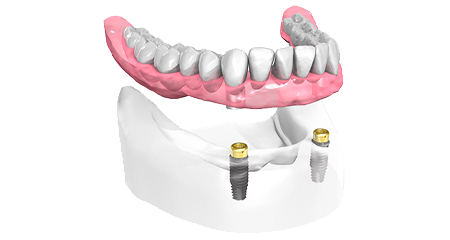

En cas d’édentement complet

Les prothèses traditionnelles mobiles constituent une solution qui rencontre en général un succès limité. Parfois douloureuses, inadaptées et gênantes, ces prothèses peuvent rendre la mastication difficile, vous empêchant de manger nombre d’aliments que vous appréciiez auparavant.

Il existe de nombreuses solutions modernes de remplacement des dents basées sur les implants dentaires.